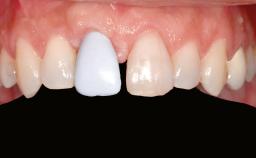

Shell Technique for Horizontal and Vertical Maxillary Bone Augmentation in a Partially Edentulous Patient with Aggressive Periodontal Disease

A 46-year-old woman was referred for treatment whose main complaints were mobility of her fixed partial dentures (right maxilla and left mandible) and periodontal bleeding during function. She also reported having taken systemic antibiotics to treat recurrent swelling in the area of the upper left molars. The patient had not seen a dentist for at least 2 years. She did not smoke and had no history of major systemic disease other than two minor orthopedic procedures some years back. The first-visit examination revealed poor plaque control, tooth mobility, periodontal disease, and a residual dentition widely associated with deep periodontal pockets.

Soft Tissue Anatomy Intact Defective

Bone Volume Horizontally and vertically sufficient Horizontally deficient Deficient vertically or deficient vertically AND horizontally